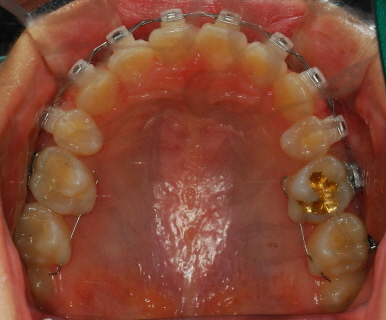

<상악 사진>

<하악사진> 저는 처음에 왜 다시 벌어지지? 하고 걱정했는데 치과선생님께서 벌리는 것이 더 어렵다고 하셨어요~ 의도된 과정이었더라구요*^^* 이번달은 고무줄을 다시! 이용하여 윗니는 뒤로 아랫니는 앞으로 당겨주는 작업을 할거에요 그래서 고무줄은 위아래로 걸게 되었습니다~ 밥먹을 때 마다 뺏다 꼈다 해야 하는데 오랜만에 다시 고무줄끼니 정말....아프네요 맛잇는거 있어도 못먹고.. 옛날에 엄마가 치아가 많이 빠져서 딱딱한거 먹는 저랑 동생들 보면서 밥먹을때마다 부럽다고 하셨었는데 지금 제가 그러니 진짜 부럽고.. 엄마께 미안한 마음도 들고 그래요..ㅠㅠ

아아 쨋든 이번달 과정은 고무줄이구요 한가지 더~ 윗니가 예전사진을 보면 앞니 뒤가 많이 울퉁불퉁 한 것을 볼 수 있는데요 윗니와 아랫니가 서로 좀 더 가깝게 하기 위해 뒷부분을 좀 깎는 작업을 했습니다 치과쌤의 표현 방식을 빌리면 일종의 배가 나온 부분을 다이어트 시켰다고나 할까요?!ㅎㅎㅎㅎ (내 배도좀 해야될듯....)